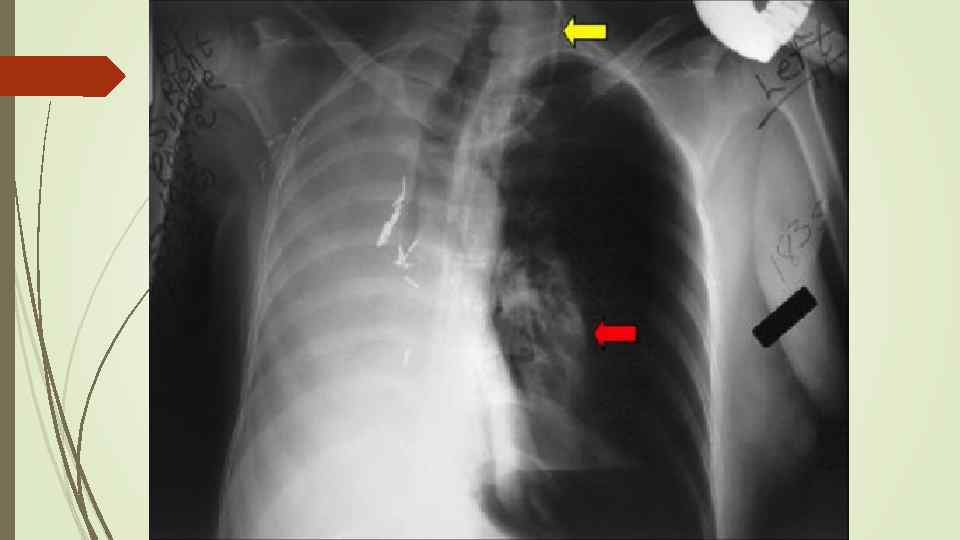

Пневмоторакс – скопление газа в плевральной полости, ведущее к спадению ткани легкого, смещению средостения в здоровую сторону, сдавлению кровеносных сосудов, опущению купола диафрагмы, что, в конечном итоге вызывает расстройство функции дыхания и кровообращения. Различают травматический, спонтанный и ятрогенный пневмоторакс. В зависимости от наличия связи с окружающей средой различают закрытый, открытый и клапанный пневмоторакс.

Пневмоторакс – скопление газа в плевральной полости, ведущее к спадению ткани легкого, смещению средостения в здоровую сторону, сдавлению кровеносных сосудов, опущению купола диафрагмы, что, в конечном итоге вызывает расстройство функции дыхания и кровообращения. Различают травматический, спонтанный и ятрогенный пневмоторакс. В зависимости от наличия связи с окружающей средой различают закрытый, открытый и клапанный пневмоторакс.

Рентгенологическое исследование: свободный газ в плевральной полости (участок просветления, лишенный легочного рисунка, расположенный на периферии легочного поля, на фоне пневмоторакса отчетливее, чем обычно, видны детали костного скелета грудной клетки) поджатое лёгкое, степень спадения которого зависит от величины пневмоторакса при напряжённом пневмотораксе средостение смещается в здоровую сторону.

Рентгенологическое исследование: свободный газ в плевральной полости (участок просветления, лишенный легочного рисунка, расположенный на периферии легочного поля, на фоне пневмоторакса отчетливее, чем обычно, видны детали костного скелета грудной клетки) поджатое лёгкое, степень спадения которого зависит от величины пневмоторакса при напряжённом пневмотораксе средостение смещается в здоровую сторону.

Гидропневмоторакс имеет такие же причины возникновения и рентгенологические проявления, как и пневмоторакс, но в плевральной полости помимо воздуха находится жидкость. Рентгенологически помимо общих признаков с пневмотораксом появляются дополнительные: - затемнение высокой интенсивности и однородной структуры, нижняя граница которого сливается с диафрагмой, а верхняя при вертикальном положении образует горизонтальный уровень; - средостение резко смещено в противоположную сторону.

Гидропневмоторакс имеет такие же причины возникновения и рентгенологические проявления, как и пневмоторакс, но в плевральной полости помимо воздуха находится жидкость. Рентгенологически помимо общих признаков с пневмотораксом появляются дополнительные: - затемнение высокой интенсивности и однородной структуры, нижняя граница которого сливается с диафрагмой, а верхняя при вертикальном положении образует горизонтальный уровень; - средостение резко смещено в противоположную сторону.